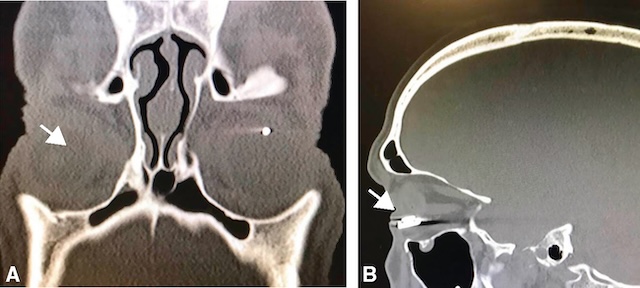

C Examens complémentaires

Dans tous les cas, à la moindre suspicion de CEIO, un examen tomodensitométrique doit être pratiqué afin de rechercher le corps étranger et, surtout, de le localiser avec précision (fig. 11.21). Il recherche en plus, selon les cas, une fracture de l’orbite, l’intégrité de la paroi oculaire, des structures intraoculaires et orbitaires, ainsi qu’un hématome orbitaire.

L’image A correspond à une coupe axiale d’un scanner orbito-facial mettant en évidence un point hyperdense dans l’orbite droite, en arrière du globe oculaire, correspondant à un corps étranger métallique intraorbitaire. L’image B, en reconstruction sagittale, confirme cette localisation : l’objet métallique apparaît comme un point blanc intense situé en arrière de la sclère, proche de la paroi postérieure de l’orbite. L’os orbitaire reste continu, sans fracture évidente. La présence du corps étranger est nette, sans artefact de diffusion, traduisant une lésion ancienne stabilisée ou bien localisée sans migration secondaire.